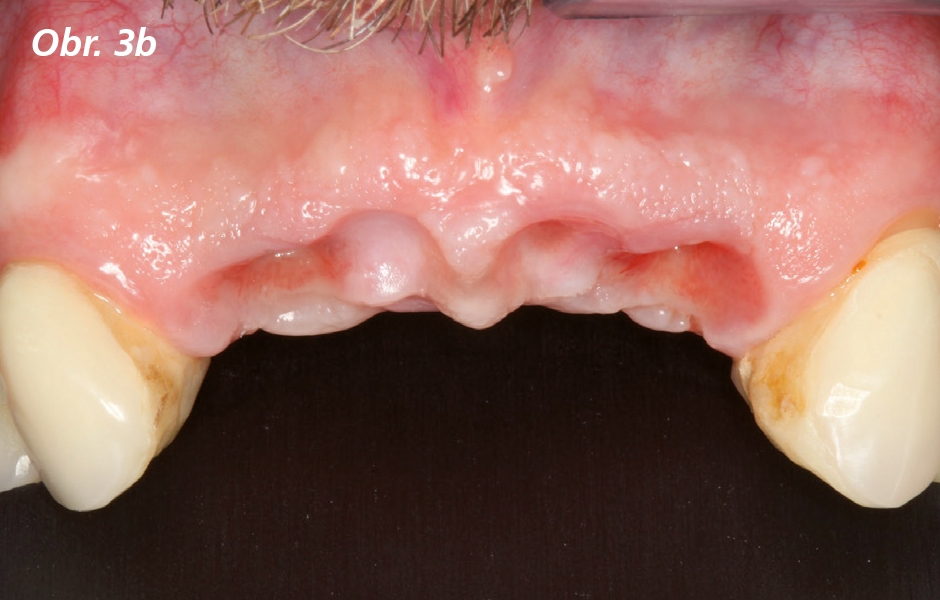

Odpověď měkkých tkání byla hodnocena každý měsíc tak, že kontury provizorní náhrady nesené implantáty byly modifikovány přidáváním nebo ubíráním akrylové pryskyřice. Tento proces se opakoval, dokud nebylo dosaženo adekvátního emergence profile a dojmu interdentální papily (obr. 3a, 3b, 4a, 4b). Šroubovaná provizorní náhrada byla odstraněna a byly zhotoveny individualizované otiskovací repliky pro zachování vytvořeného emergence profile. Poté byl otevřenou technikou sejmut otisk na úrovni implantátu za použití polyvinyl siloxanu (Aquasil Ultra Monophase and XLV; Dentsply Caulk). Byla zhotovena definitivní náhrada a odevzdání bylo provedeno obvyklým způsobem (obr. 5). Pooperační poučení bylo uděleno spolu s instruktáží orální hygieny. Pacient byl zařazen do počátečního tříměsíčního recallu za účelem kontroly hygieny a verifikace okluzních vztahů.

Frontální pohled na výchozí situaci / kontury měkkých tkání po třech měsících – stav měkkých tkání byl hodnocen každý měsíc